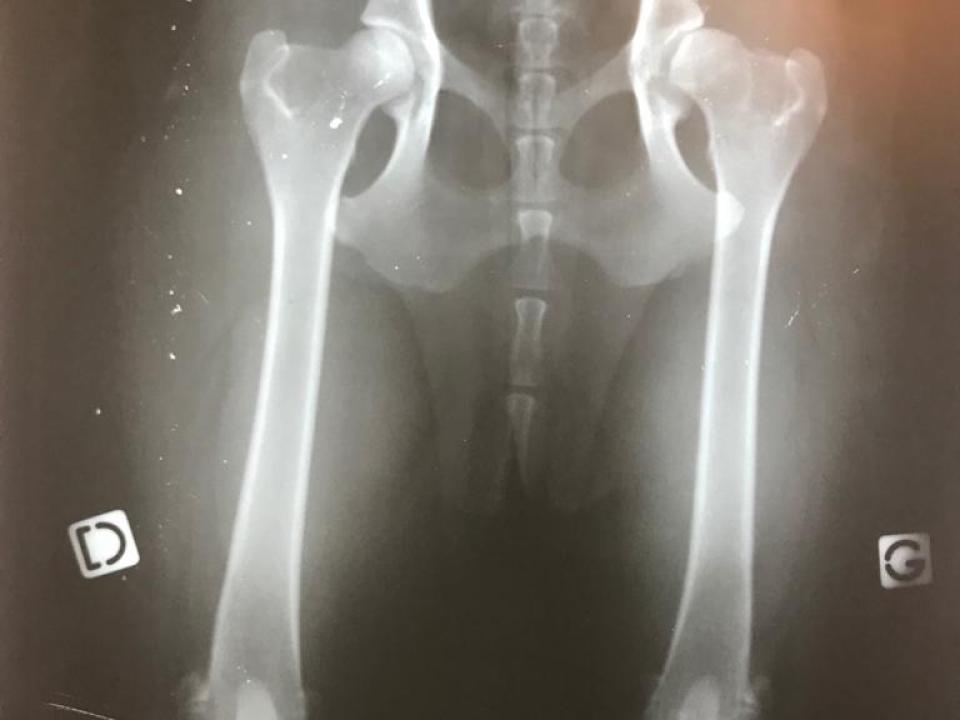

Sur cette radiographie de mon Berger Australien Ollie, on distingue la hanche gauche (G = dysplasie) et la hanche droite (D = saine).